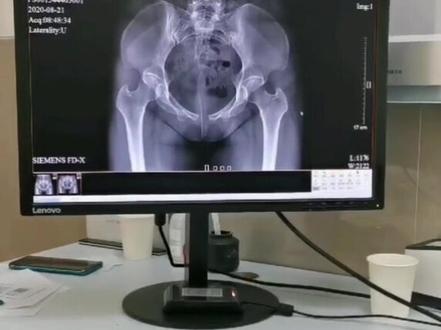

如何测量耻骨分离啊?今天这个视频呢,教大家如何在家里就能自测耻骨事故分离。首先呢,我们可以找一个皮尺或者是千分尺,嗯,平躺在床上,嗯, 放在我们刺骨的这个前端的两侧,你可以用手摸一下,刺骨的两边呢,都有点尖尖的位置,就是我们的刺骨前端。 可能的测量如果呢,正常的我们的女性呢是四到六公分,如果呢已经达到五公分以上呢,那就是属于耻骨分离的症 状态,好多女性呢都已经达到八公分或者是十公分。刺骨分离呢,第一它会造成会造成我们的刺骨前韧带酸痛或者疼痛的感觉发长,刺骨的侧位挤压我们的膀胱,导致排尿。

耻骨分开了,叫耻骨的联合分离,这些产妇就不要提倡他非得去多走路啊,因为这耻骨呢是两块,他到中间呢, 靠韧带结合在一起,随着孕周有些在随这个儿头往骨盆腔走,互联合分离的情况呢,并不是非常少见,那么这种情况呢,我建议可以带一个托腹带,减轻一些对耻骨局部的压迫。 一个像这些产妇呢,就不要提倡他非得去多走路啊,他的运动也要做一些适合自己的运动来减轻这些症状。